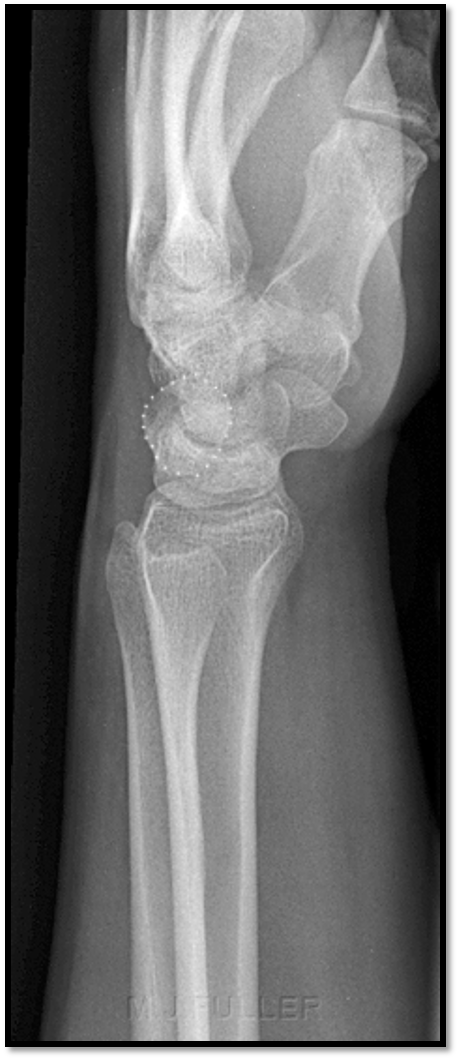

Q

What is the positioning fault?

How would you fix it?

A

• CMC joints are closed - caused by extension of the wrist

• 2nd MC obscuring trapezoid/trapezium

• flex wrist so its flat on IR to open joint spaces